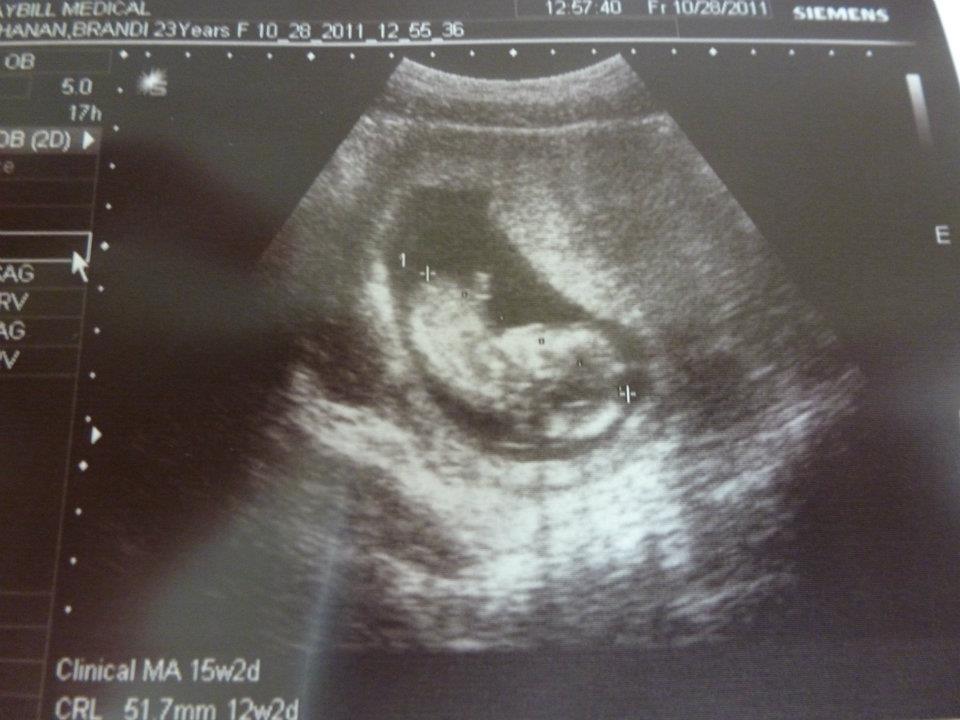

I Have heard of the ramzi theory of the place of the placenta for boy or girl. After two girl on 3 the other 8 months my husband and i decided to try for our boy which will be our last baby...with both my girls we had sex every other day i elevated with my hips under a pillow pointed towards the ceiling did it from behind and i did not orgasm. with this one i only had sex once 12 hours before ovulation stuck baking soda up my you know what orgasmd first did the reverse cowgirl and elevated with my butt in the air since my cervix is towards the front i wanted the semen to fall onto it. the first picture is my first daughter at 12 weeks and the picture is on the abdomen...the second picture is my second daughter at 12 weeks on the abdomen...and the third is the new baby at 8 weeks 4 days through the vagina....any guesses

Attachment 24081Attachment 24082Attachment 24083